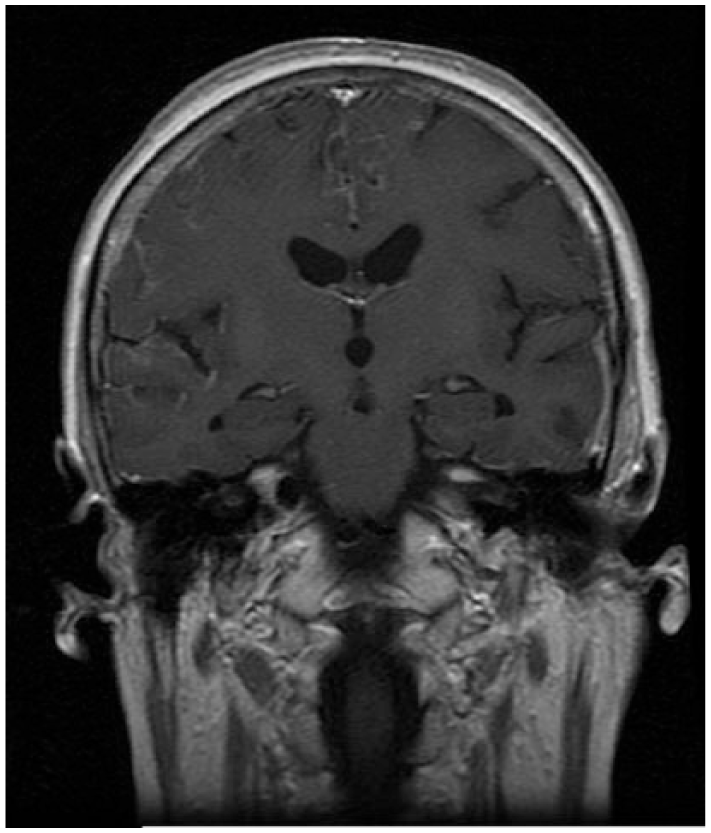

Linear or nodular enhancing lesions of the cranial nerves and spinal nerve roots (e.g. cauda equine), brain sulci and cerebellar foliae are the most common findings32,33 (Figures 1–3). NM lesions typically are small in size (<5 mm) and with complex geometry, thus a quantitative analysis with current MRI technology is difficult. 34 Other neuroimaging techniques (MRI spectroscopy, MRI perfusion, MRI diffusion and positron emission tomography) are not currently employed. Communicating hydrocephalus could be observed in 11–17% of patients, and CSF flow studies, including radioisotope cisternography, are useful in the case of suspected CSF blockage or altered intrathecal drug delivery.35,36

Enhanced lesions in brain sulci.